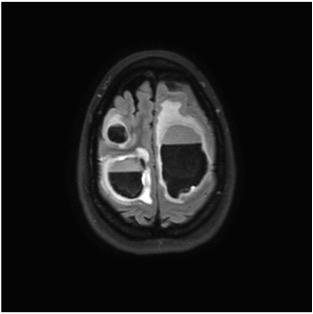

To study the hypothesis that radiation to the hippocampal stem cells plays a role in cognitive decline, 518 patients were randomized to whole brain radiotherapy plus memantine with or without hippocampal avoidance. The results of the clinical trial found a 26 percent relative reduction in risk of cognitive toxicity following whole brain radiation therapy with hippocampal avoidance versus whole-brain radiotherapy. The cognitive function benefit of hippocampal avoidance did not differ by age.

Over time, patients who received treatment that avoided the hippocampus continued to maintain measurable improvements in cognition. They self-reported fewer neurologic symptoms, less interference of neurologic symptoms with their daily activities and fewer problems remembering things in their daily lives. These patients experienced toxicity, intracranial progression-free survival and overall survival outcomes similar to those experienced by patients who had whole-brain radiotherapy.